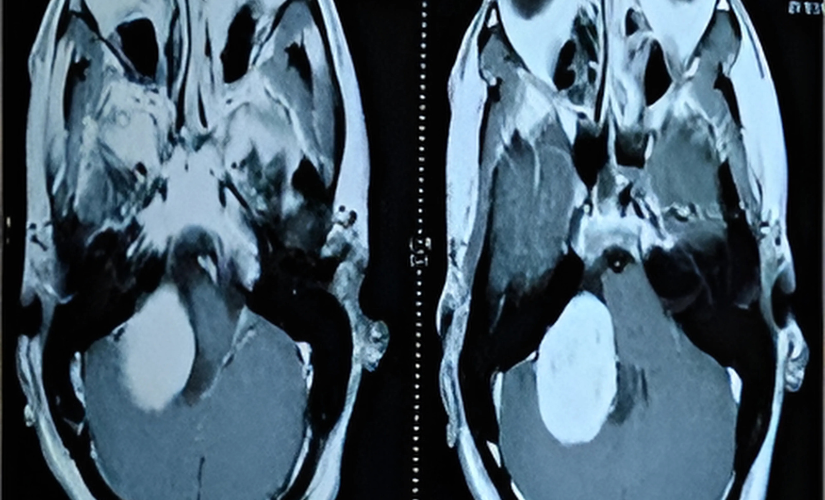

Symptoms depend on tumor size, location, and nerves affected, including headaches, facial weakness or numbness, vision changes, hearing loss, difficulty swallowing or speaking, balance problems, and hydrocephalus-related symptoms like nausea and vomiting. Diagnosis usually involves detailed neurological examinations along with imaging modalities like MRI and CT scans to map tumor extent and involvement of adjacent structures.

Through neurological exams and detailed imaging like MRI and CT scans.